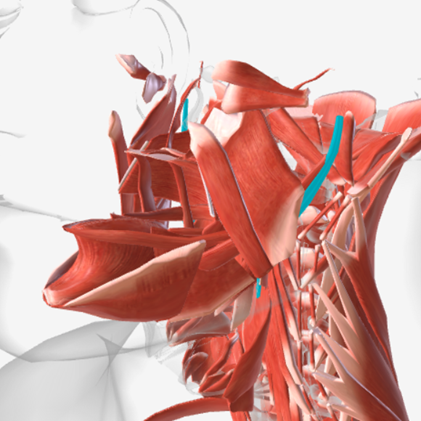

Superior pharyngeal constrictor

origin is on the pterygomandibular raphe, coursing posteriorly to insert on the median raphe of the pharyngeal aponeurosis function is to pull the pharyngeal wall forward to constrict the pharyngeal diameter

Middle pharyngeal constrictor

origin is on the horns of the hyoid and stylohyoid ligament, coursing up and back to the median pharyngeal raphe; function is to narrow the diameter of the pharynx

Inferior pharyngeal constrictor

origin is the oblique line of the thyroid laminae, coursing up and back to insert on the median pharyngeal raphe; function is to reduce the diameter of the lower pharynx

Cricopharyngeus

origin is the cricoid cartilage, coursing back to the orifice of the esophagus; function is to constrict the superior orifice of the esophagus; also referred to as the upper esophageal sphincter

Salpingopharyngeus

origin is the lower margin of the auditory tube, coursing down to insert into the palatopharyngeus muscle; function is to elevate the lateral pharyngeal wall

Stylopharyngeus

origin is the styloid process, coursing down to insert into the pharyngeal constrictors and the posterior thyroid cartilage; function is to elevate and open the pharynx